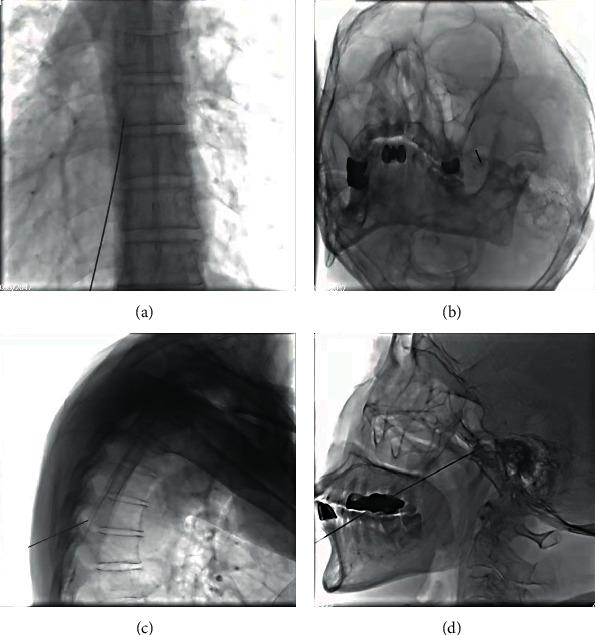

Under the guidance of a digital subtraction angiography (DSA) machine, via fluoroscopic imaging techniques, patients diagnosed with herpes zoster neuralgia at the subacute stage, where self-reported pain lasts between 30 and 90 days, were treated with nerve pulsed radiofrequency surgery combined with intravenous lidocaine infusion or saline infusion as control. This study explores the clinical efficacy, safety, and clinical value of the combined treatment compared with nerve pulsed radiofrequency surgery alone.

In this study, 72 patients diagnosed with herpes zoster neuralgia at the subacute stage were randomly divided into two groups with matched gender, age, and clinical symptoms. Both groups received pulsed radiofrequency surgery for the affected nerve segments under DSA fluoroscopy. Five days after the operation, 0.9% saline was administered daily for five consecutive days (50 ml per day, intravenous infusion) to group A ( = 36), and lidocaine was administered daily for five consecutive days (3 mg per kg per day, intravenous infusion) to group B ( = 36). Patients with poor pain control during the treatment were given 10 mg morphine tablets for pain relief to reach visual analog scale (VAS) ≤4 points. Data of the following categories were collected: VAS score, self-rating anxiety scale (SAS) score, depression self-rating scale (SDS) score, Pittsburgh sleep quality score (PSQI), 45 body area rating scale score, skin temperature measurement using infrared thermography, analgesic drug use before and after treatment at six different time points: before surgery ( ), one day after surgery ( ), three days after surgery ( ), five days after surgery ( ), one month after surgery ( ), and two months after surgery ( ). Blood was collected from all patients in the morning before surgery and right after the last intravenous infusion of lidocaine at . Serum inflammatory indexes including white blood cell count, lymphocyte count, neutrophils count, erythrocyte sedimentation rate count, C-reactive protein (CRP) level, calcitonin gene-related peptide (CGRP) level, and interleukin-6(IL-6) level were determined. Lastly, the incidence of complications and adverse reactions throughout the study was recorded.